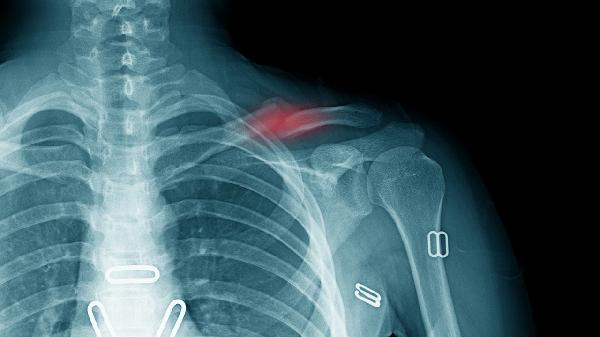

锁骨骨折会有后遗症吗

锁骨骨折多数情况下不会留下后遗症,但少数患者可能出现骨折不愈合、畸形愈合或肩关节功能障碍等问题。锁骨骨折通常由直接暴力或跌倒时手臂伸展着地引起,建议患者及时就医并遵循医嘱进行康复。

锁骨骨折后若得到及时复位和固定,局部血供恢复良好,骨折端对位稳定,愈合过程通常顺利。早期进行适度的肩关节功能锻炼有助于维持关节活动度,防止肌肉萎缩。康复期间避免提重物或剧烈运动,可减少并发症风险。定期复查X线片能监测骨折愈合进展,确保骨骼正常重塑。

部分患者因骨折严重移位或固定不当,可能出现愈合延迟或骨不连。感染或软组织损伤较重时,可能影响局部血液循环,导致慢性疼痛或肩部活动受限。长期不进行康复训练可能引起肩关节僵硬,影响日常生活功能。年龄较大或合并骨质疏松的患者愈合能力较弱,需延长康复周期。